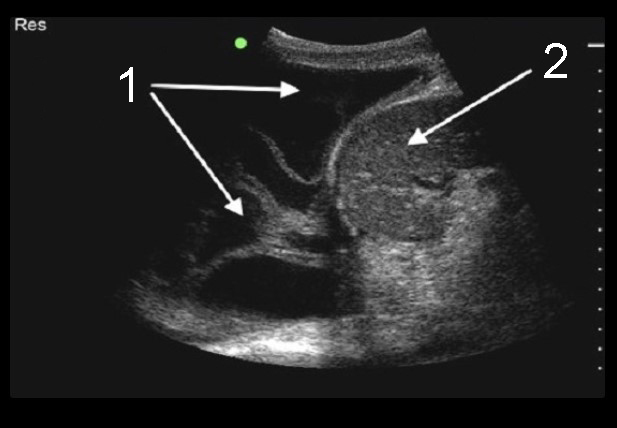

Thoracentesis Sagittal Septated Pleural Effusion Image

Septated Fluid

Liver